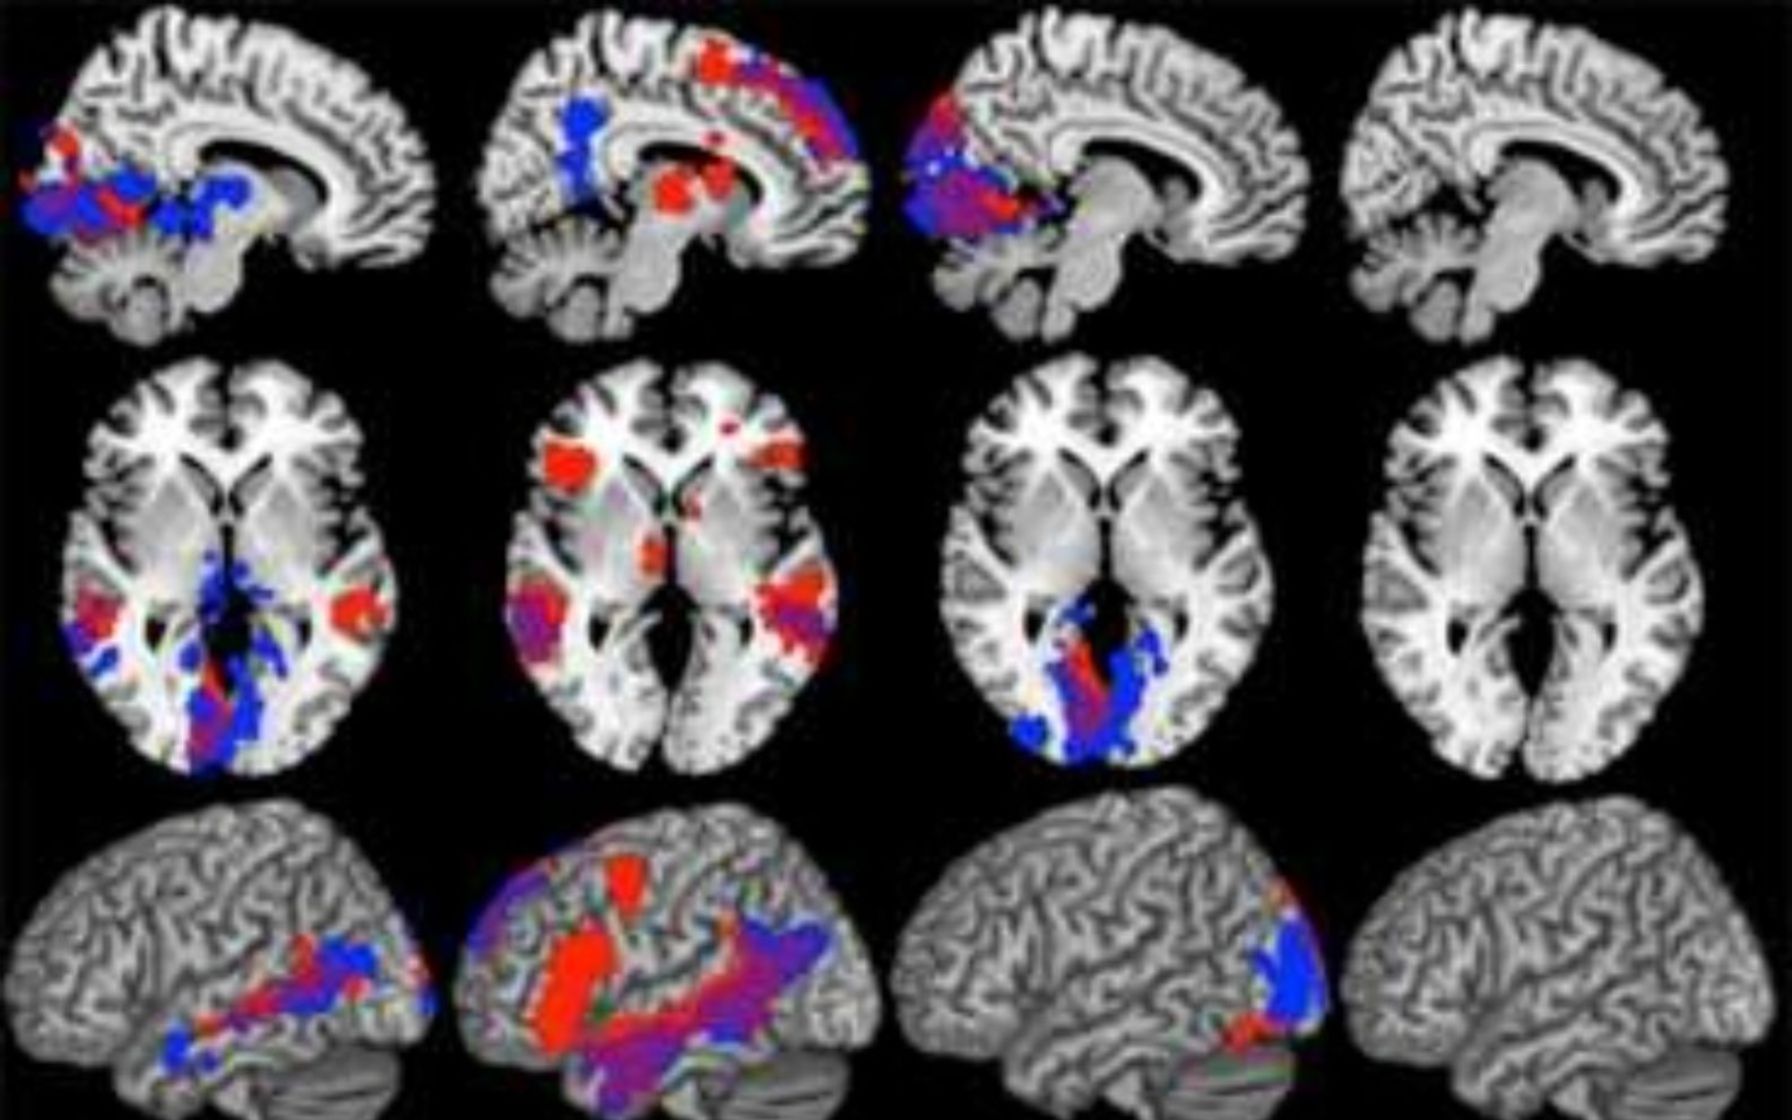

Brain Xray Analysis